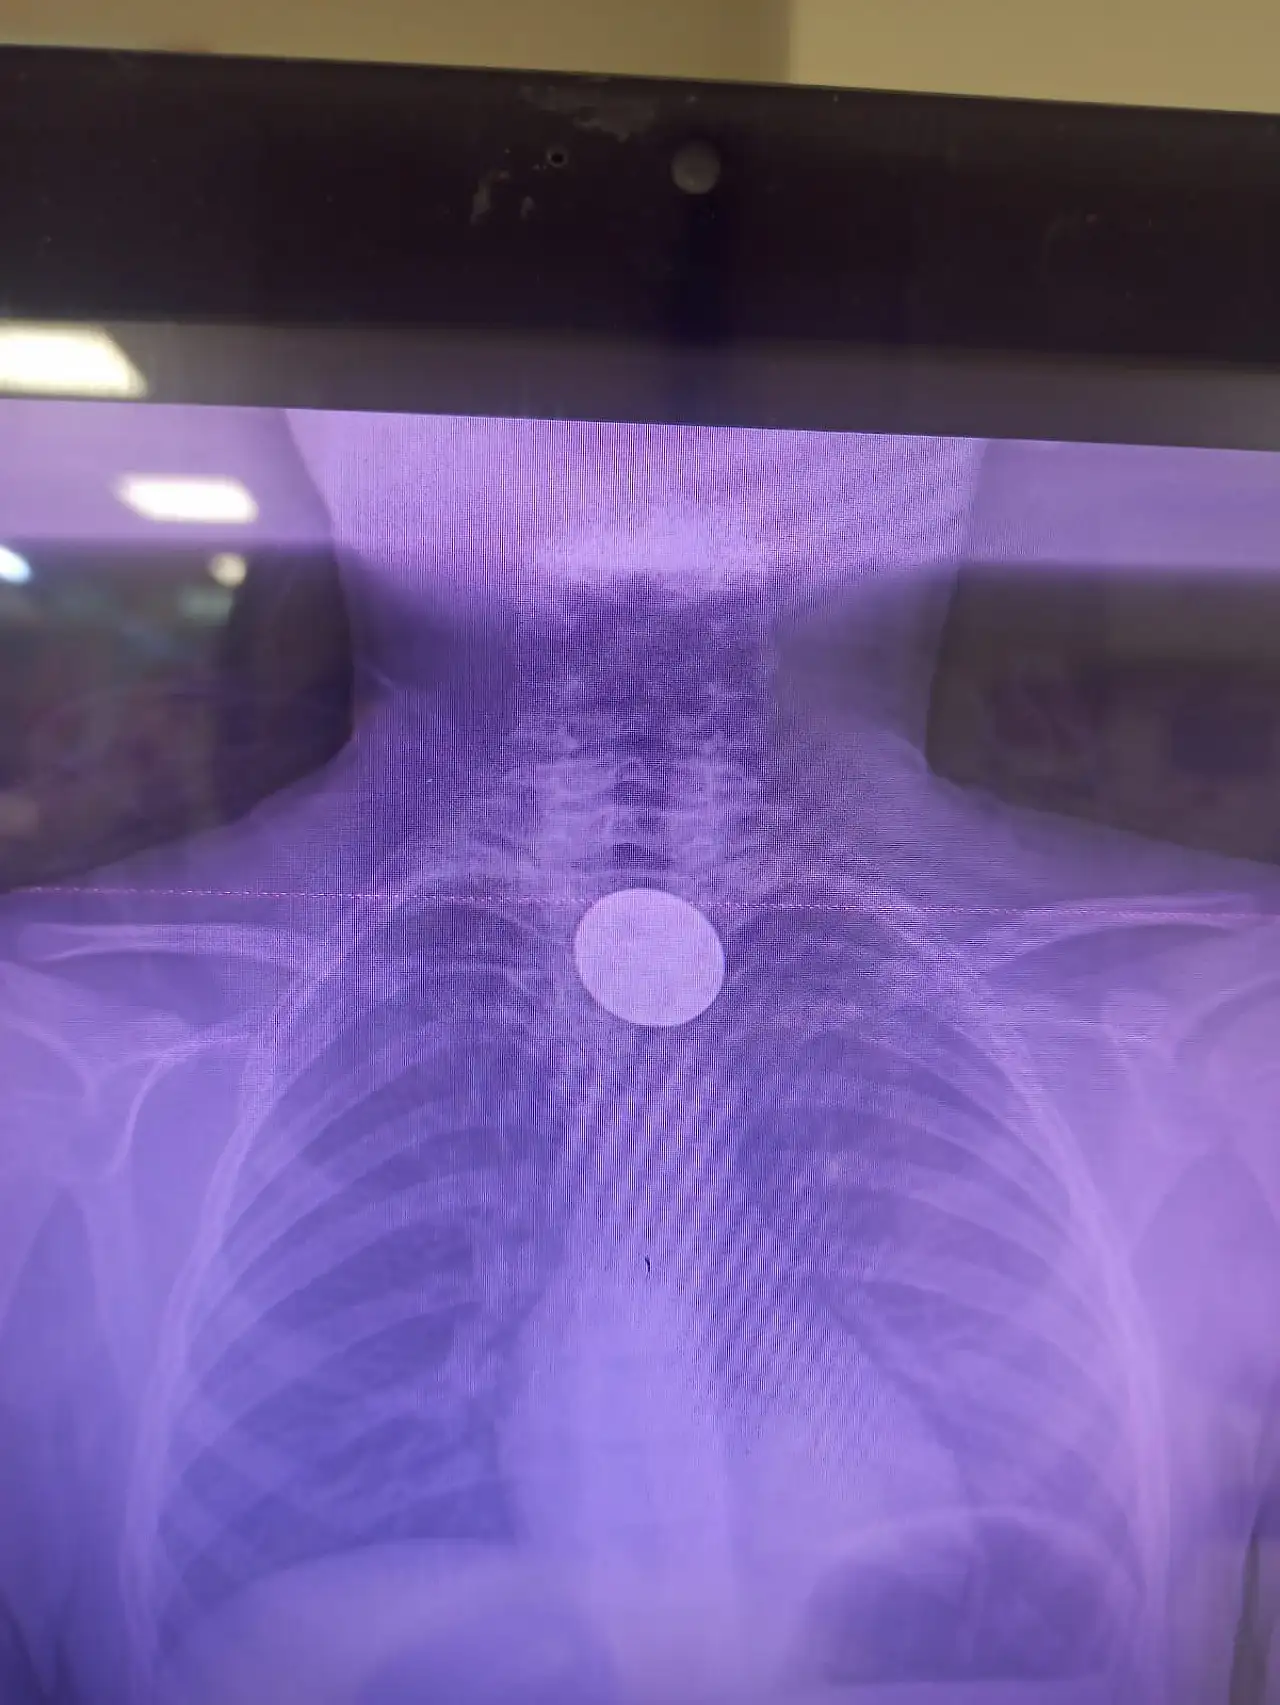

Siirt'te 5 TL'lik madeni para yutan 8 yaşındaki çocuk, Siirt Eğitim ve Araştırma Hastanesi'nde gerçekleştirilen başarılı bir müdahale ile sağlığına kavuştu.

Edinilen bilgilere göre, yabancı cisim yutma şikâyetiyle hastaneye getirilen Y.K., yapılan ilk muayene ve görüntüleme tetkiklerinin ardından operasyona alındı. Yapılan incelemelerde madeni paranın çocuğun yemek borusuna kadar ilerlediği belirlendi.

Gastroenteroloji Uzmanı Dr. Yaren Dirik ile Kulak Burun Boğaz (KBB) Hekimi Dr. Yasin Gökçınar’ın koordineli çalışmasıyla gerçekleştirilen müdahalede, madeni para herhangi bir komplikasyona yol açmadan çıkarıldı.